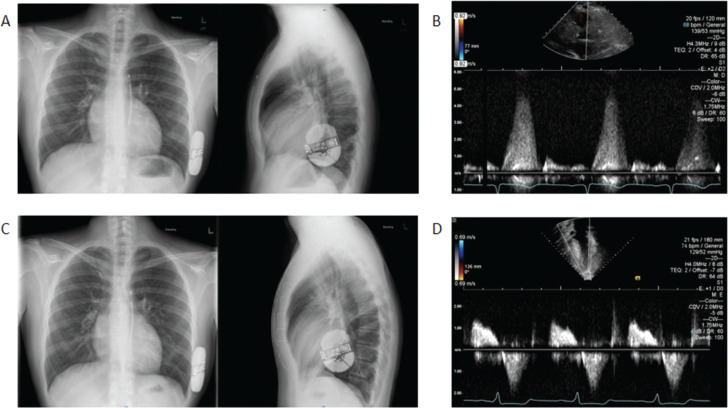

肥厚性心肌病(HCM)是一种遗传性疾病,发病率为1 / 500,是儿童心源性猝死的最常见原因。我们提出一个17岁的HCM和一级预防皮下植入式心脏转复除颤器(S-ICD)的男孩谁发展为左心室流出道阻塞和左冠状动脉前降支心肌桥。患者接受了室间隔肌切除术/肌切开术和肌桥拆除术。S-ICD系统在手术过程中未受干扰,没有功能丧失。在维持S-ICD功能的情况下,在最佳S-ICD放置后,儿童HCM患者可以完成室间隔肌切除术。

Hypertrophic cardiomyopathy (HCM) is an inherited disease present in 1 in 500 individuals and is the most common cause of sudden cardiac death in children. We present the case of a 17-year-old boy with HCM and a primary prevention subcutaneous implantable cardioverter-defibrillator (S-ICD) who developed left ventricular outflow tract obstruction and a myocardial bridge of the left anterior descending coronary artery. The patient underwent a septal myectomy/myotomy and muscular bridge unroofing. The S-ICD system was undisturbed during the surgery, with no loss of function. Septal myectomy may be accomplished in pediatric HCM patients following optimal S-ICD placement with maintained S-ICD function.